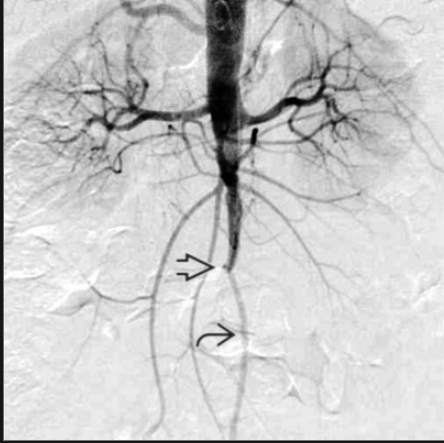

Patient presenting with absent femoral pulses, bilateral buttock claudication, impotence

Abdominal aortic occlusion//Leriche Syndrome

chronic, with collaterals (atherosclerosis, hypertension, diabetes mellitus, smoking history)

acutely can be caused by severe dehydration, hypercoagulable state, embolized atrial myxoma

Leriche syndrome = abdominal aortic or iliac artery occlusive disease that causes absent femoral pulses, bilateral buttock claudication, and impotence. Surgical therapy (aorto-bi-iliac or aorto-bifemoral bypass) is the treatment of choice.